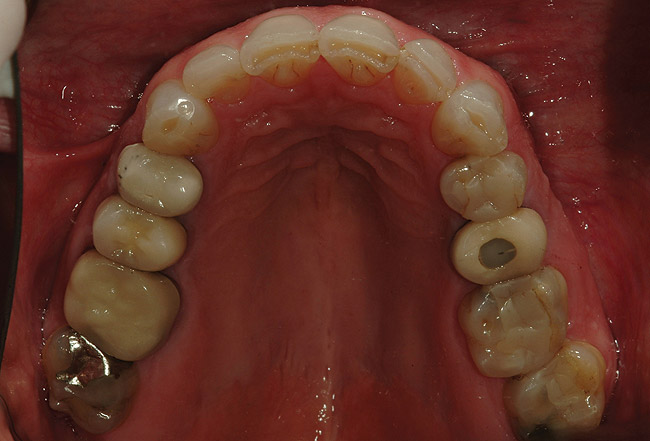

Figure 8  Preoperative view of the upper arch.

Figure 8

A 50-year-old, highly stressed businessman presented with severe wear on all teeth. The excessive wear developed over time because of a combination of age and malocclusion (Figure 1 and Figure 2). After the initial examination and consultation, the patient agreed to treatment in three phases using lithium-disilicate all-ceramic restorations (IPS e.max® Press, Ivoclar Vivadent, www.ivoclarvivadent.com). The patient was adamant about starting with “just the front upper 10” (ie, teeth Nos. 4 through 13). Restoration of teeth Nos. 20 through 29 was planned as the second stage, and the molars would be treated last.